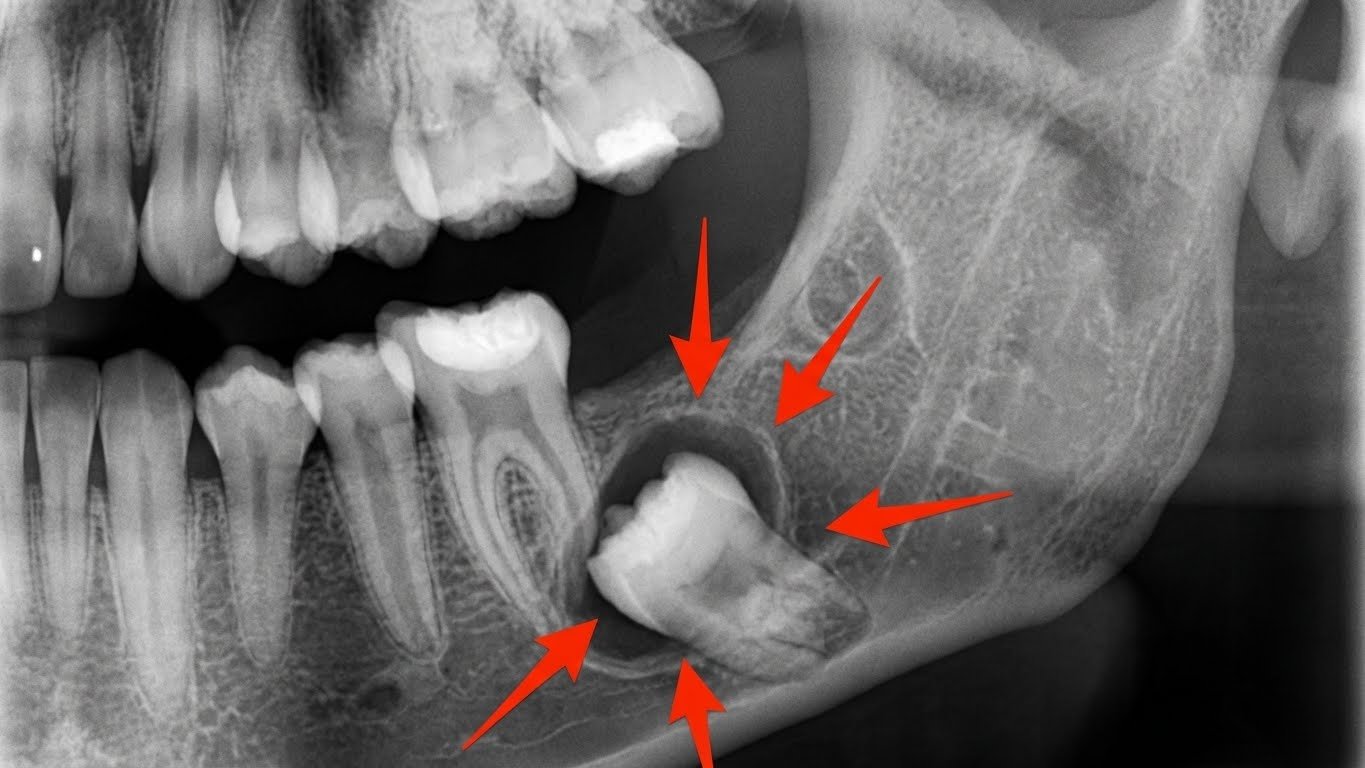

5. Formação de Cistos ou Lesões ao Redor do Dente

Um Sinal Sério que Requer Atenção Imediata

A formação de cistos ao redor dos dentes do siso é um dos sinais mais sérios de que você precisa extrair o siso. Embora seja menos comum que os outros sinais mencionados, é uma complicação que pode ter consequências graves se não for tratada.

O Que São Cistos Dentários

Um cisto dentário é uma bolsa cheia de líquido que se forma ao redor de um dente incluso ou impactado. Os cistos se desenvolvem a partir do folículo dentário (o saco que envolve o dente em desenvolvimento) e podem crescer lentamente ao longo do tempo.

Sintomas e Riscos

Muitas vezes, os cistos são assintomáticos nos estágios iniciais e são descobertos apenas através de radiografias de rotina. No entanto, à medida que crescem, podem causar:

- Inchaço na mandíbula ou maxila: Você pode notar uma protuberância ou assimetria facial

- Dor ou desconforto: Quando o cisto atinge um tamanho significativo

- Deslocamento de dentes: O cisto pode empurrar os dentes adjacentes

- Enfraquecimento do osso: Cistos grandes podem enfraquecer a estrutura óssea da mandíbula

- Infecção: Cistos podem se infectar, causando dor intensa e inchaço

- Risco de fratura mandibular: Em casos extremos, o enfraquecimento do osso pode levar a fraturas

Tipos de Lesões

Além dos cistos, outras lesões podem se formar ao redor dos sisos inclusos:

- Ameloblastoma: Um tumor benigno que pode ser agressivo localmente

- Granulomas: Massas de tecido inflamatório

- Tumores odontogênicos: Crescimentos que se originam dos tecidos dentários

Diagnóstico e Tratamento

Os cistos e lesões são geralmente identificados através de radiografias panorâmicas ou tomografias computadorizadas. Se um cisto for detectado, a extração do dente do siso é essencial, geralmente acompanhada da remoção completa do cisto. Em alguns casos, pode ser necessário realizar o procedimento em ambiente hospitalar, especialmente se o cisto for grande.

Prevenção Através de Exames Regulares

Este é mais um motivo para manter suas consultas odontológicas regulares e realizar radiografias periódicas. A detecção precoce de cistos permite um tratamento mais simples e previne complicações graves.